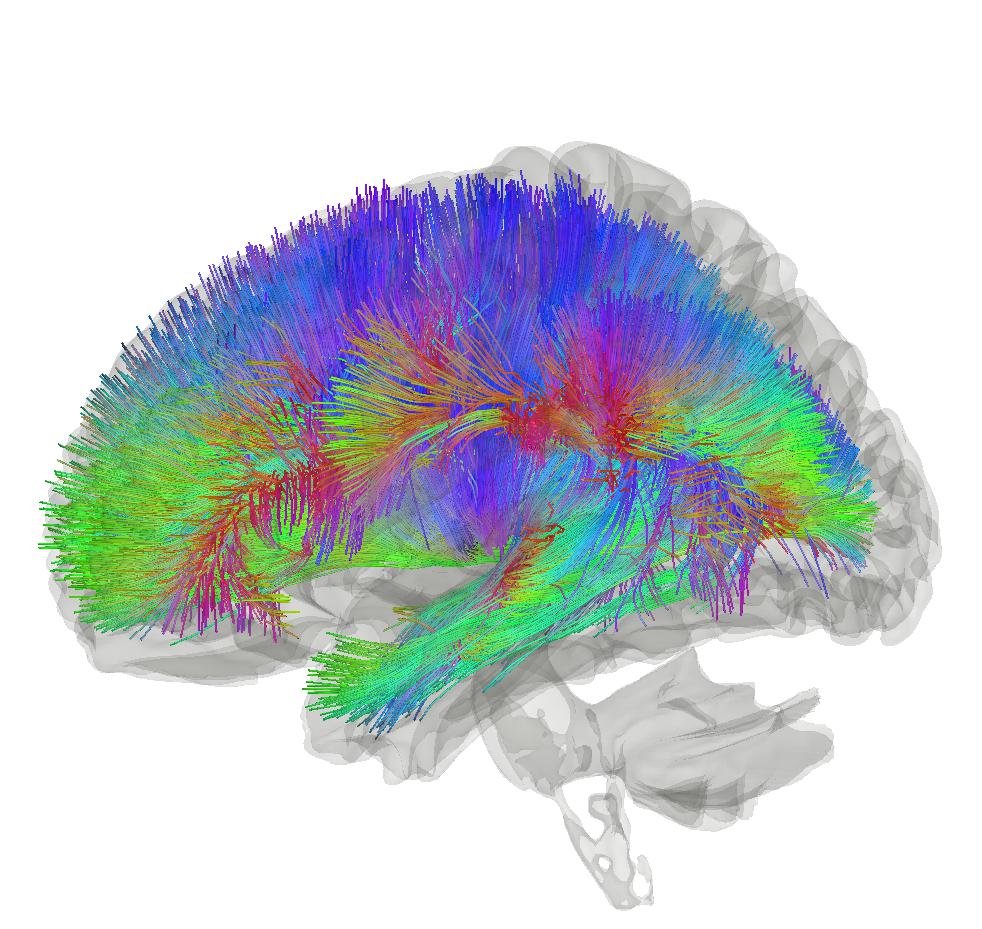

Tractography: Yeh, F. C., Panesar, S., Fernandes, D., Meola, A., Yoshino, M., Fernandez-Miranda, J. C., … & Verstynen, T. (2018). Population-averaged atlas of the macroscale human structural connectome and its network topology. NeuroImage, 178, 57-68. – http://brain.labsolver.org/, Wikimedia Commons/ CC BY-SA 4.0, https://commons.wikimedia.org/w/index.php?curid=78298711